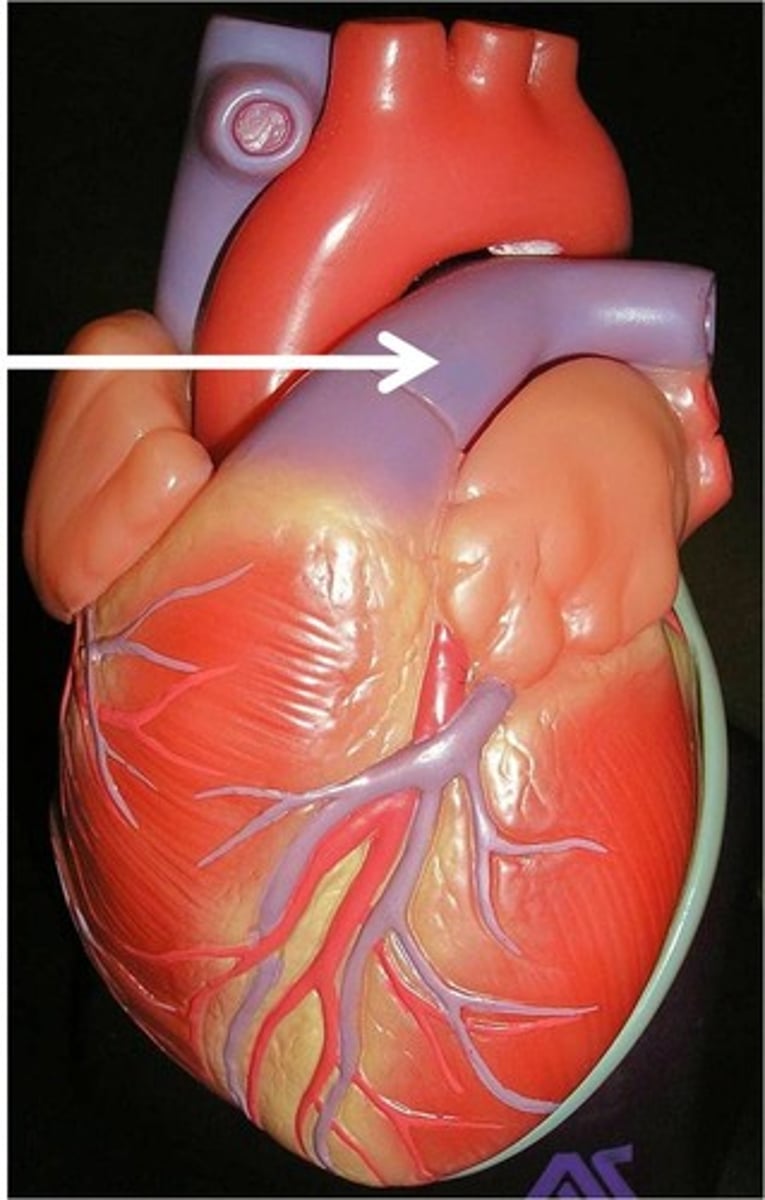

anterior interventricular sulcus

the junction between right and left ventricles

anterior side (depression)

Identify the vessel

right pulmonary artery

anterior interventricular artery

in the anterior interventricular sulcus